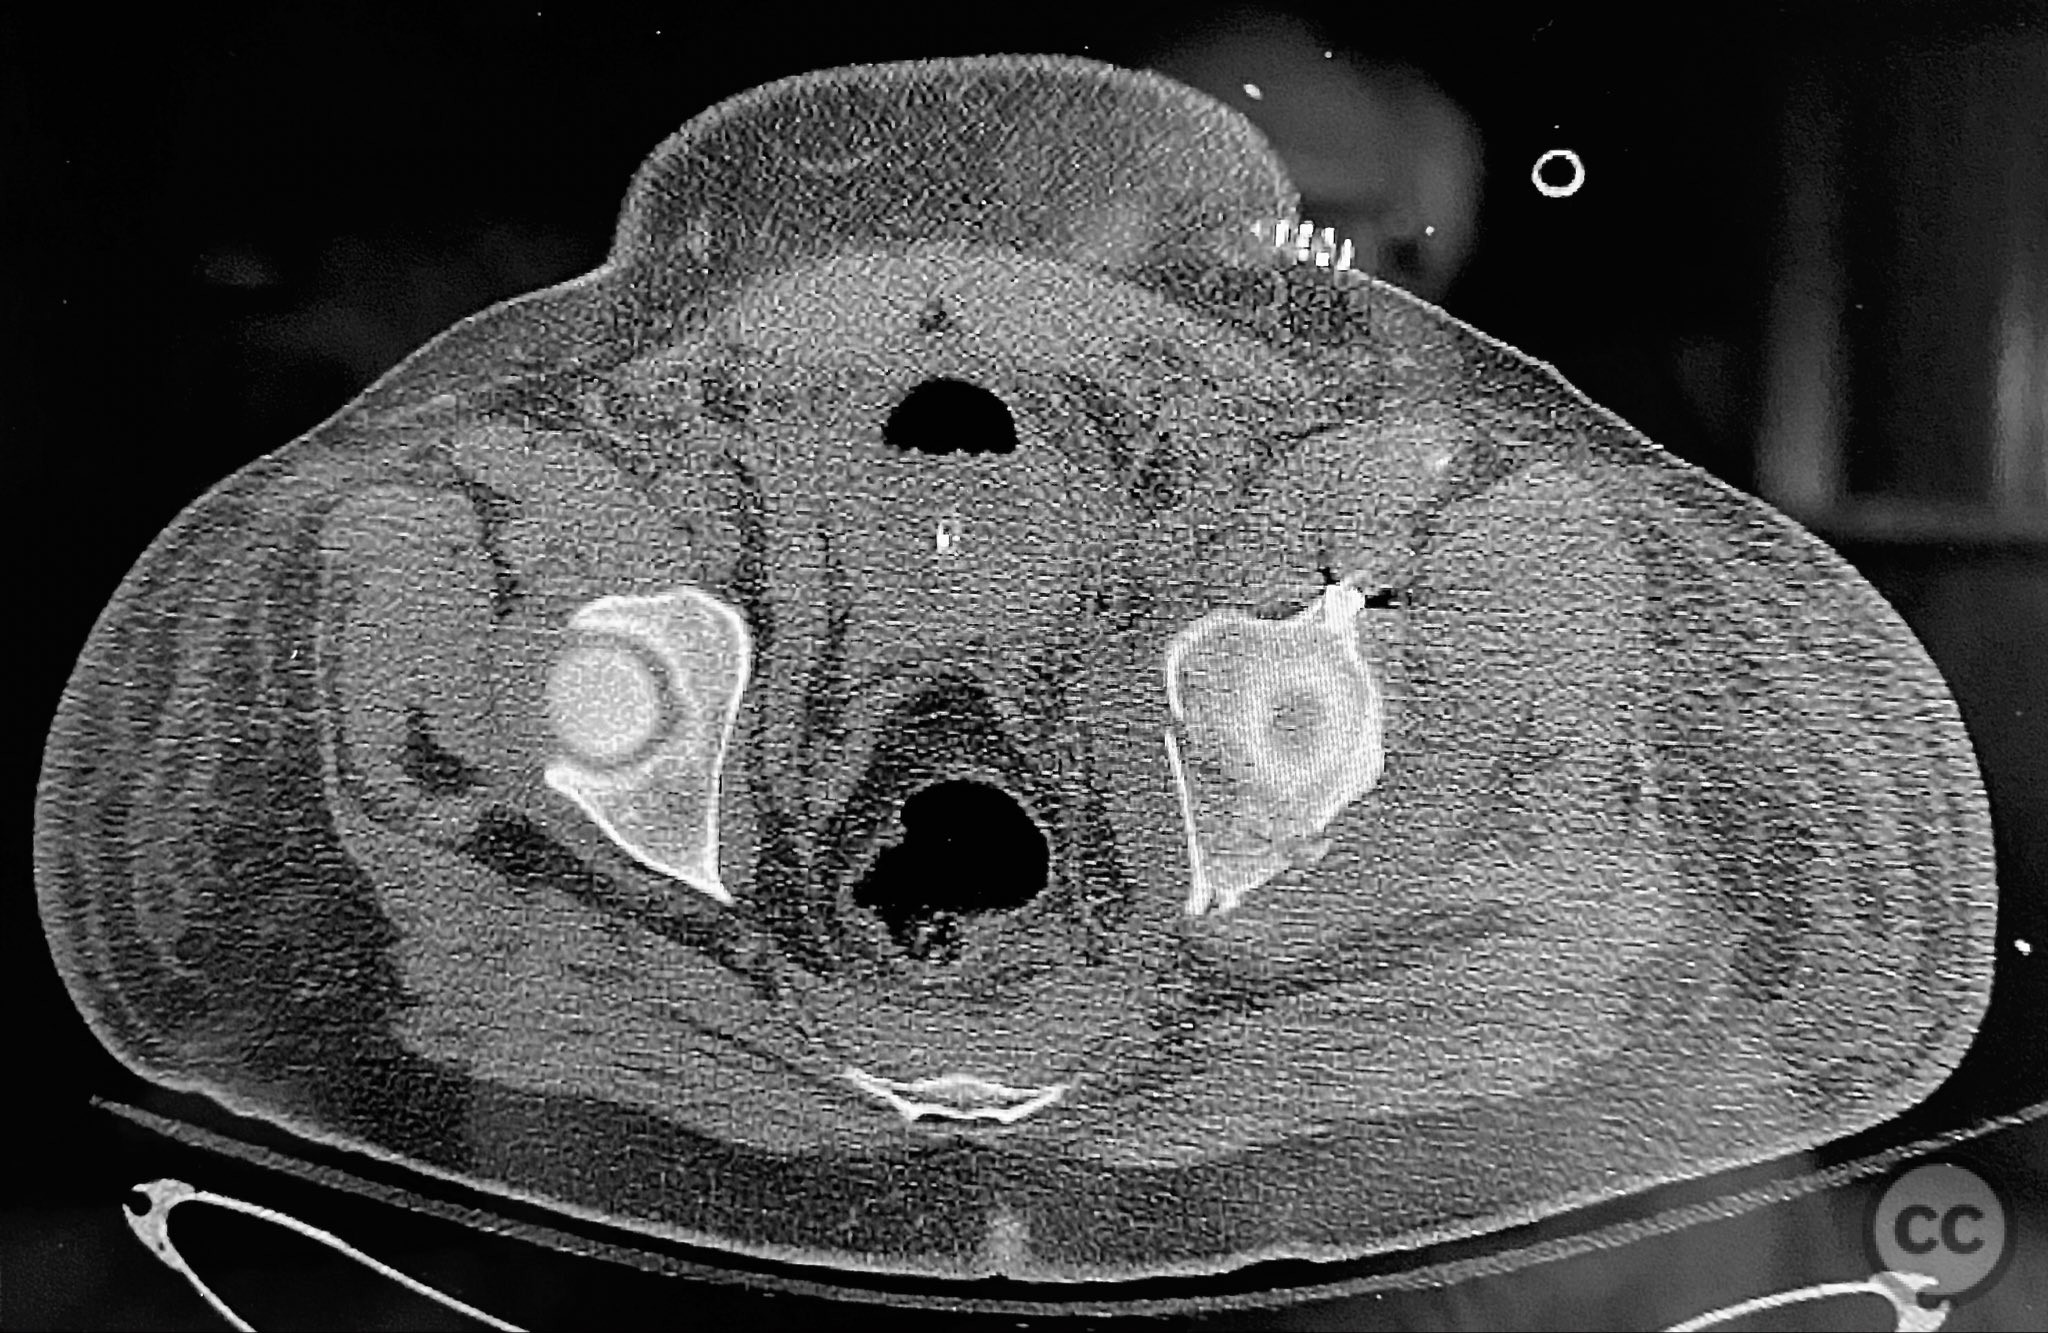

Clinical and radiological findings:  A patient presented with a displaced associated both column acetabular fracture, characterized radiographically by the presence of the "spur sign" on the anteroposterior (AP) pelvis film, indicating the caudal aspect of the intact ilium exposed by medial displacement of the articular fragments. The spur was more clearly visualized on the obturator oblique rendered image. Axial computed tomography (CT) images demonstrated the intact ilium, medially displaced anterior column (AC) and posterior column (PC) fragments, and provided detailed visualization of surrounding soft tissues, including vascular structures enhanced by contrast. Multiplanar CT reconstructions (axial, sagittal, coronal) and 3D renderings were utilized for comprehensive fracture and soft tissue assessment. The patient’s overall clinical condition was a significant factor in surgical planning.